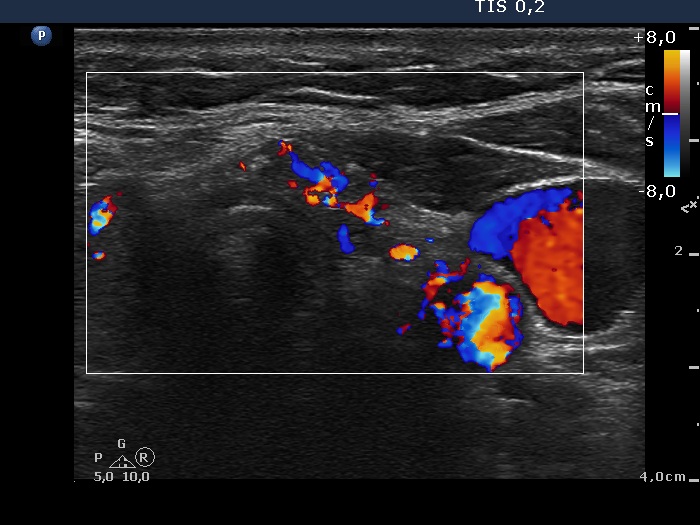

Left lobe, transverse scan, color Doppler mode. The vascularization is increased.